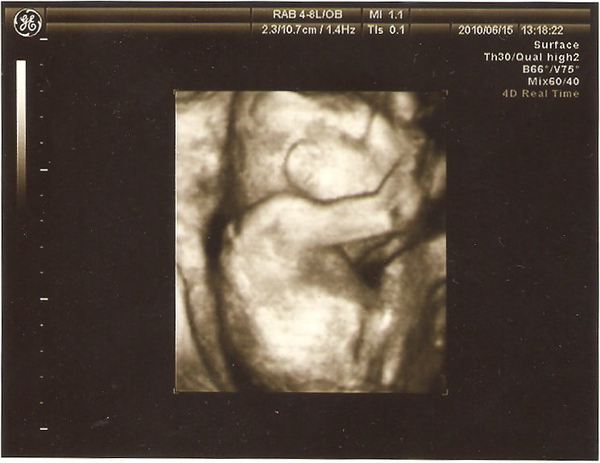

這張照片讓我們覺得:以後鼻子應該不會跟他老爸一樣扁...

今天檢查數據,6/15這天正好滿22週,除肚圍正好符合週數外,其他通通超前,尤其腿長一直都有超前一週

最後這一張..............知道的就知道,可憐的李小果,好沒隱私喔..............

恭喜恭喜~